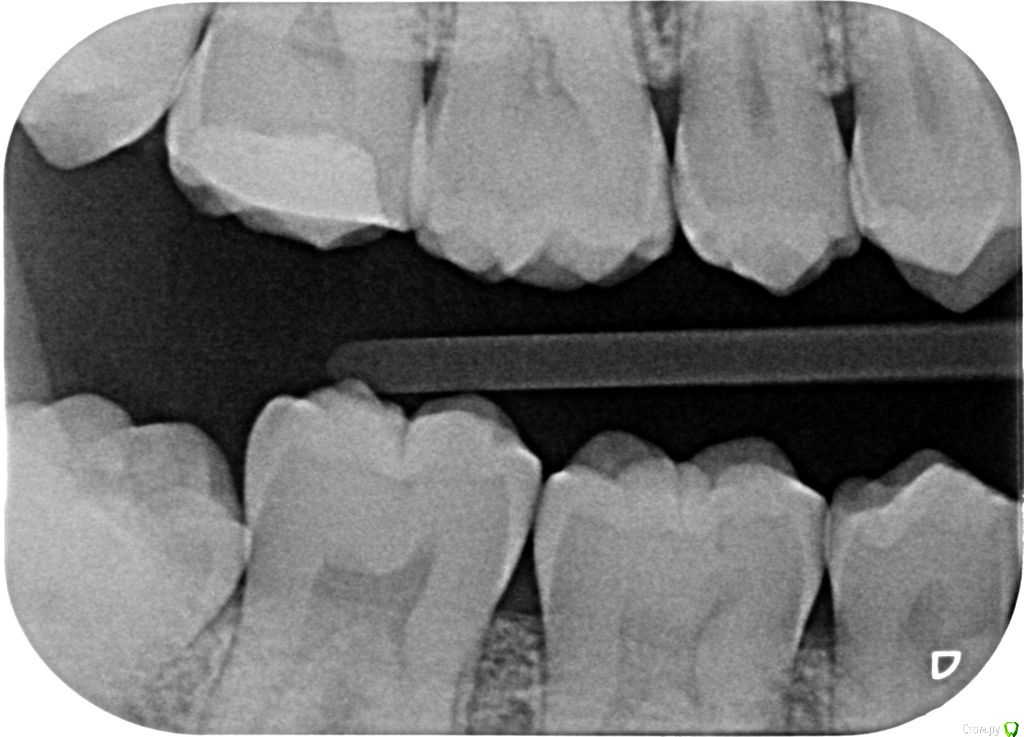

janis1 Опубликовано 14 декабря, 2015 Автор Поделиться Опубликовано 14 декабря, 2015 Итак, продолжение моей эпопеи.Удалось попасть к челюстно-лицевому хирургу-онкологу раньше чем было запланировано. После очного осмотра и изучения КТ, профессор выдал заключение, что никаких проблем по его части он не нашел.После этого я был у терапевта, по поводу 25 -26 зубов, ничего кроме зубного камня на 26 зубе (кстати напомню я недавно делал гигиену ) он так-же ничего не нашел.На всякий случай сделали рентген зубов, даже как я понял с двух сторон, вот снимки: Ну и самое главное - проблема осталась, то-есть уже более двух месяцев я живу с болью в районе верхней челюсти...Что делать дальше не знаю...Очень надеюсь на вашу помощь! Ссылка на комментарий